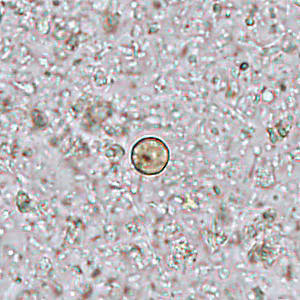

Several people developed gastrointestinal symptoms of watery diarrhea, nausea with vomiting, and low-grade fever approximately 1 week after attending a catered event. Stool specimens were collected for laboratory testing which included a formalin-ethyl acetate concentration with brightfield wet mount examination. Figures A–D show what was observed at 400x magnification in all of the specimens. The objects of interest shown ranged in size from 8 to 10 micrometers What is your diagnosis? What other test(s), if any, would you recommend?

Figure A